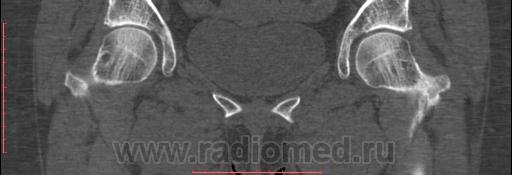

А это КТ

Асептического артроза не вижу. В правой головке есть киста по КТ.

+1. То же есть и слева, но меньше по размерам. Вывод- дистрофические измененеия в тазбедреных суставах есть однозначно. Остаётся вопрос, на основании каких же признаков,по денситометрии, так категорично высказались за наличие асептическогь некроза?

По КТ: сколько даме лет? ДОА I ст, кисты головок бёдер. Эностоз не в счет.

А некроза нет. Ни септического, ни асептического - никакого.

Полностью согласен - артроз и все, а кистозная перестройка, очень в артроз 2ст. вкладывается. Это и хотели доказать. А всё к тому, что любой метод может давать ошибку. И денситометрия. И врача -рентгенолога, которого обвинили в пропуске "некроза" мы, с Вашей помощью, реабилитировали.